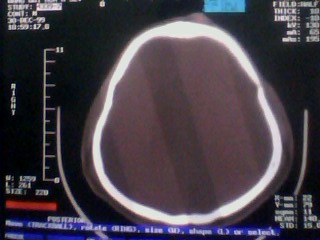

以下是引用随光逐影在2010-1-7 14:49:00的发言:[br]1)结合病史,考虑多发性脑转移瘤可能性大;建议行ct增强扫描检查。2)大脑镰下疝。3)脑积水。